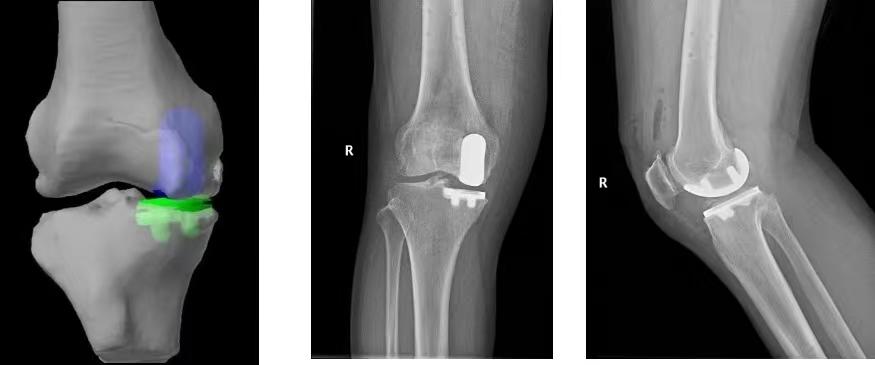

手术前,医生先通过CT扫描生成3D骨骼模型,帮助医生制定手术方案。同时,预判假体型号大小,使假体与患者骨骼完全匹配。

准备就绪后,医生在MAKO机器人辅助下,为陈女士完成单髁置换术。

据介绍,单髁关节置换术的手术视野有限,传统手术中,医生要靠肉眼判断容易出现误差。而MAKO机器人可在术中通过“触觉反馈”实时提示医生磨骨、截骨的范围,以及假体安装的深度和角度。比如说,锯子只会在安全范围内工作,一旦“出圈”机械臂动力就会自动停止,这样就可以避免骨头周围重要结构的损伤。

“机器人部分替代了医生的眼和手,而且眼更准、手更稳,医生就不会担心传统手术中敲击假体过浅导致固定不牢固,或者打入过深而导致骨折,可以避免手术中和手术后并发症的发生,大大提高了手术的安全性。与此同时提高了手术的精准性,医生可在机器人的辅助下将关节假体放置在恰当的位置,误差可以控制在1°和1毫米以内。”李之琛解释。